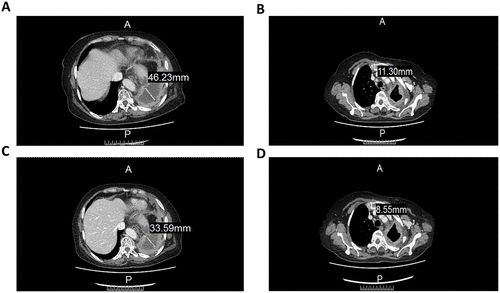

经3周期的治疗后,CT图像显示细胞疗法在治疗肿瘤方面具有一定的疗效。具体来说,左肺包裹的胸腔内液体从46.22mm减少到 33.59mm(图 2A ~2C),而前气管-后腔静脉间质区域的淋巴结从11.3mm减少到8.55mm(图2B~2D)。